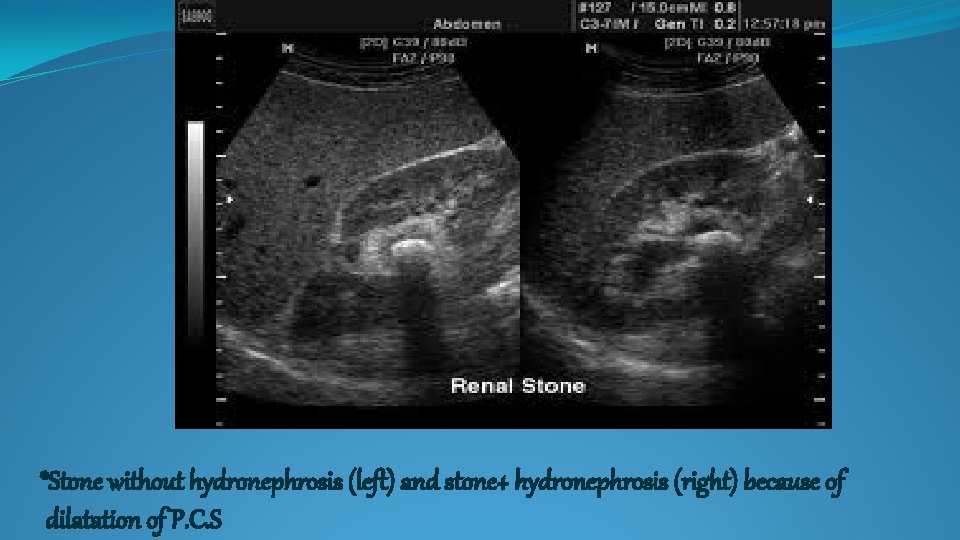

*Stone without hydronephrosis (left) and stone+ hydronephrosis (right) because of dilatation of P. C.

*Stone without hydronephrosis (left) and stone+ hydronephrosis (right) because of dilatation of P. C. S